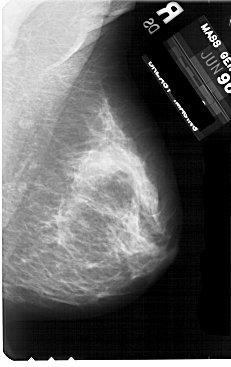

A_1725_1.RIGHT_MLO

RIGHT_MLO LINES 5491 PIXELS_PER_LINE 3451 BITS_PER_PIXEL 12 RESOLUTION 43.5 NON_OVERLAY